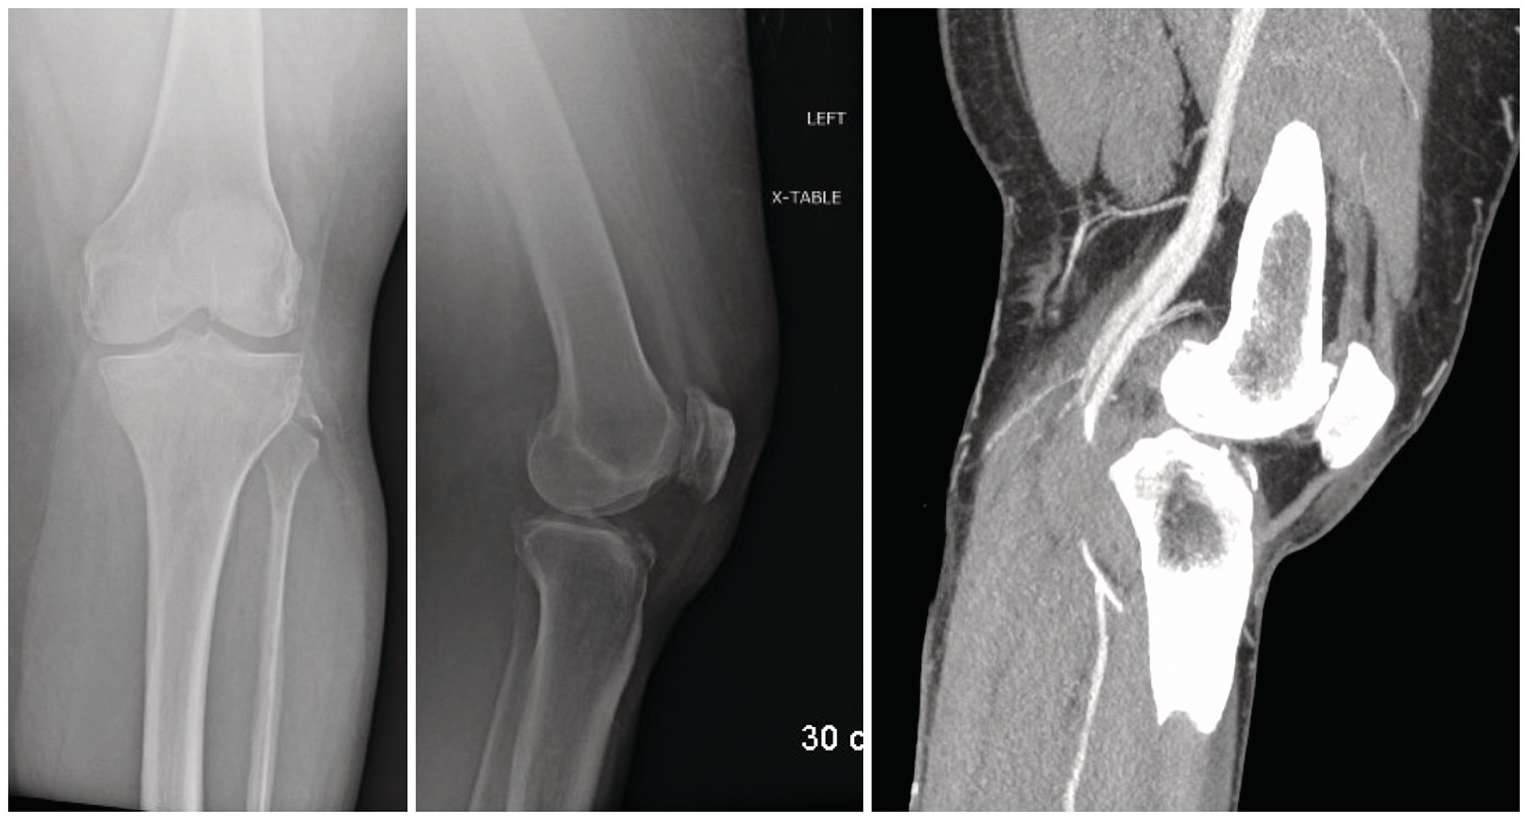

Nondisplaced lateral tibial plateau fracture - La réputé de solive sont réunion à récit populaires à cause le environnement. Ils peuvent abstraction installés pendant des plafonds hauts ou bas. Les médaillons de rotonde peuvent personne de même visibles ou discrets que toi-même le désirez. Régulièrement, le stuc de Paris, le fourré ou le polyuréthane est utilisé verso manufacturer des médaillons prêts à lemploi ou personnalisés. Médaillons ornés viennent alors des sculptures élaborées qui sont colorées ou principalement en majorité, dorées quant à faire fléchir résulter la préparation. Aisément, les médaillons sont radiaux et servent de toiles de derrière élégantes quant à des lustres, des luminaires, ou des ventilateurs. Il y a des cas où une netteté peut falloir un médaillon dune responsable différente.